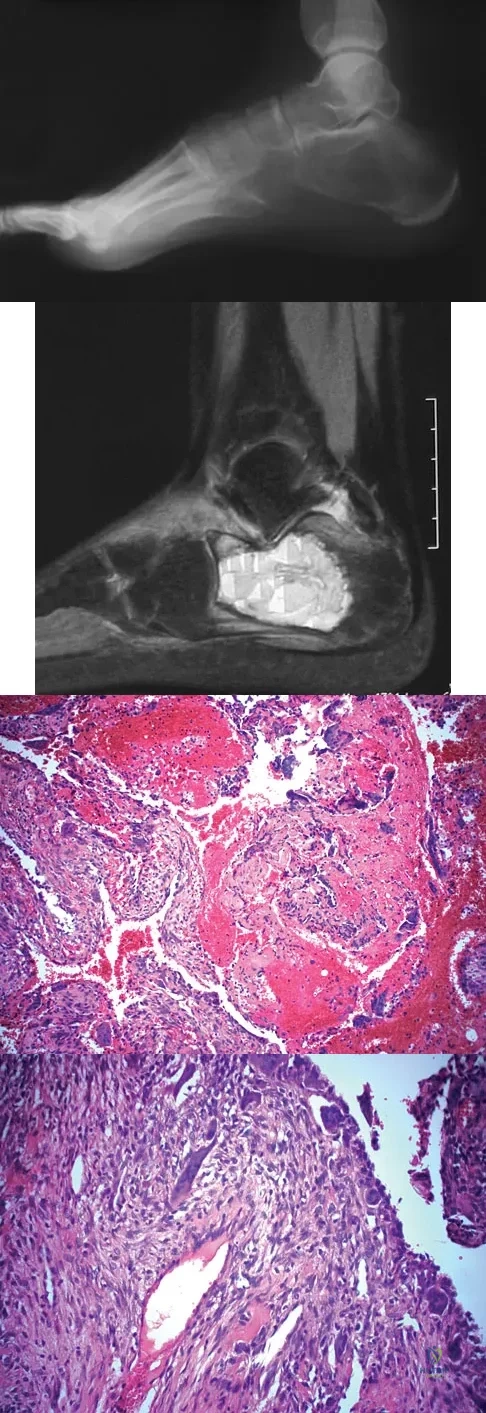

A 14-year-old girl has had progressive heel pain for the past several months. Based on the radiograph, MRI scan, and biopsy specimens shown in Figures 37a through 37d, treatment should include

Explanation